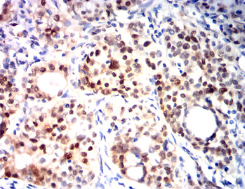

KMT2A Mouse Monoclonal antibody[7E1D]

This gene encodes a transcriptional coactivator that plays an essential role in regulating gene expression during early development and hematopoiesis. The encoded protein contains multiple conserved functional domains. One of these domains, the SET domain, is responsible for its histone H3 lysine 4 (H3K4) methyltransferase activity which mediates chromatin modifications associated with epigenetic transcriptional activation. This protein is processed by the enzyme Taspase 1 into two fragments, MLL-C and MLL-N. These fragments reassociate and further assemble into different multiprotein complexes that regulate the transcription of specific target genes, including many of the HOX genes. Multiple chromosomal translocations involving this gene are the cause of certain acute lymphoid leukemias and acute myeloid leukemias. Alternate splicing results in multiple transcript variants.

Immunogen :   Purified recombinant fragment of human KMT2A (AA:150-400) expressed in E. Coli.

IHC    1/200 - 1/1000